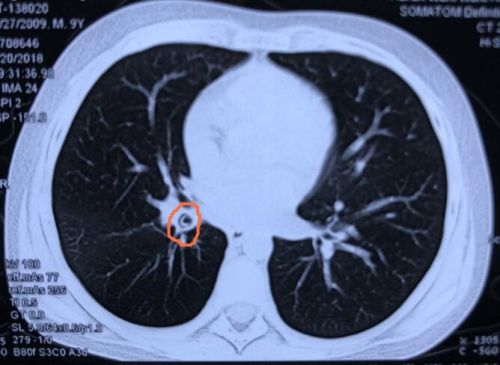

ct显示,异物(红圈内)卡在右侧主支气管。

耳鼻咽喉头颈外科二病室。8月28日,耳鼻咽喉头颈外科二病室主任刘斌教授带领医护人员运用支气管镜,从孩子的右侧主支气管内取出一枚2×1.5cm大小的笔帽。由于在体内留存时间太长,笔帽被大量的肉芽组织和脓液所包裹。